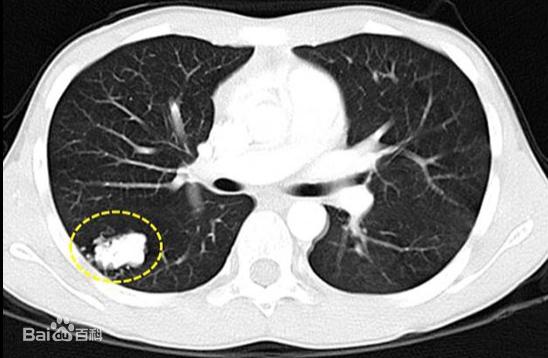

肺癌的早期筛查率得到了明显提高

也发现了越来越多的肺部结节

甚至部分患者的肺结节被诊断为肺癌

已完成10余例肺结节手术

大部分为早期恶性肿瘤

(来源:百度百科)